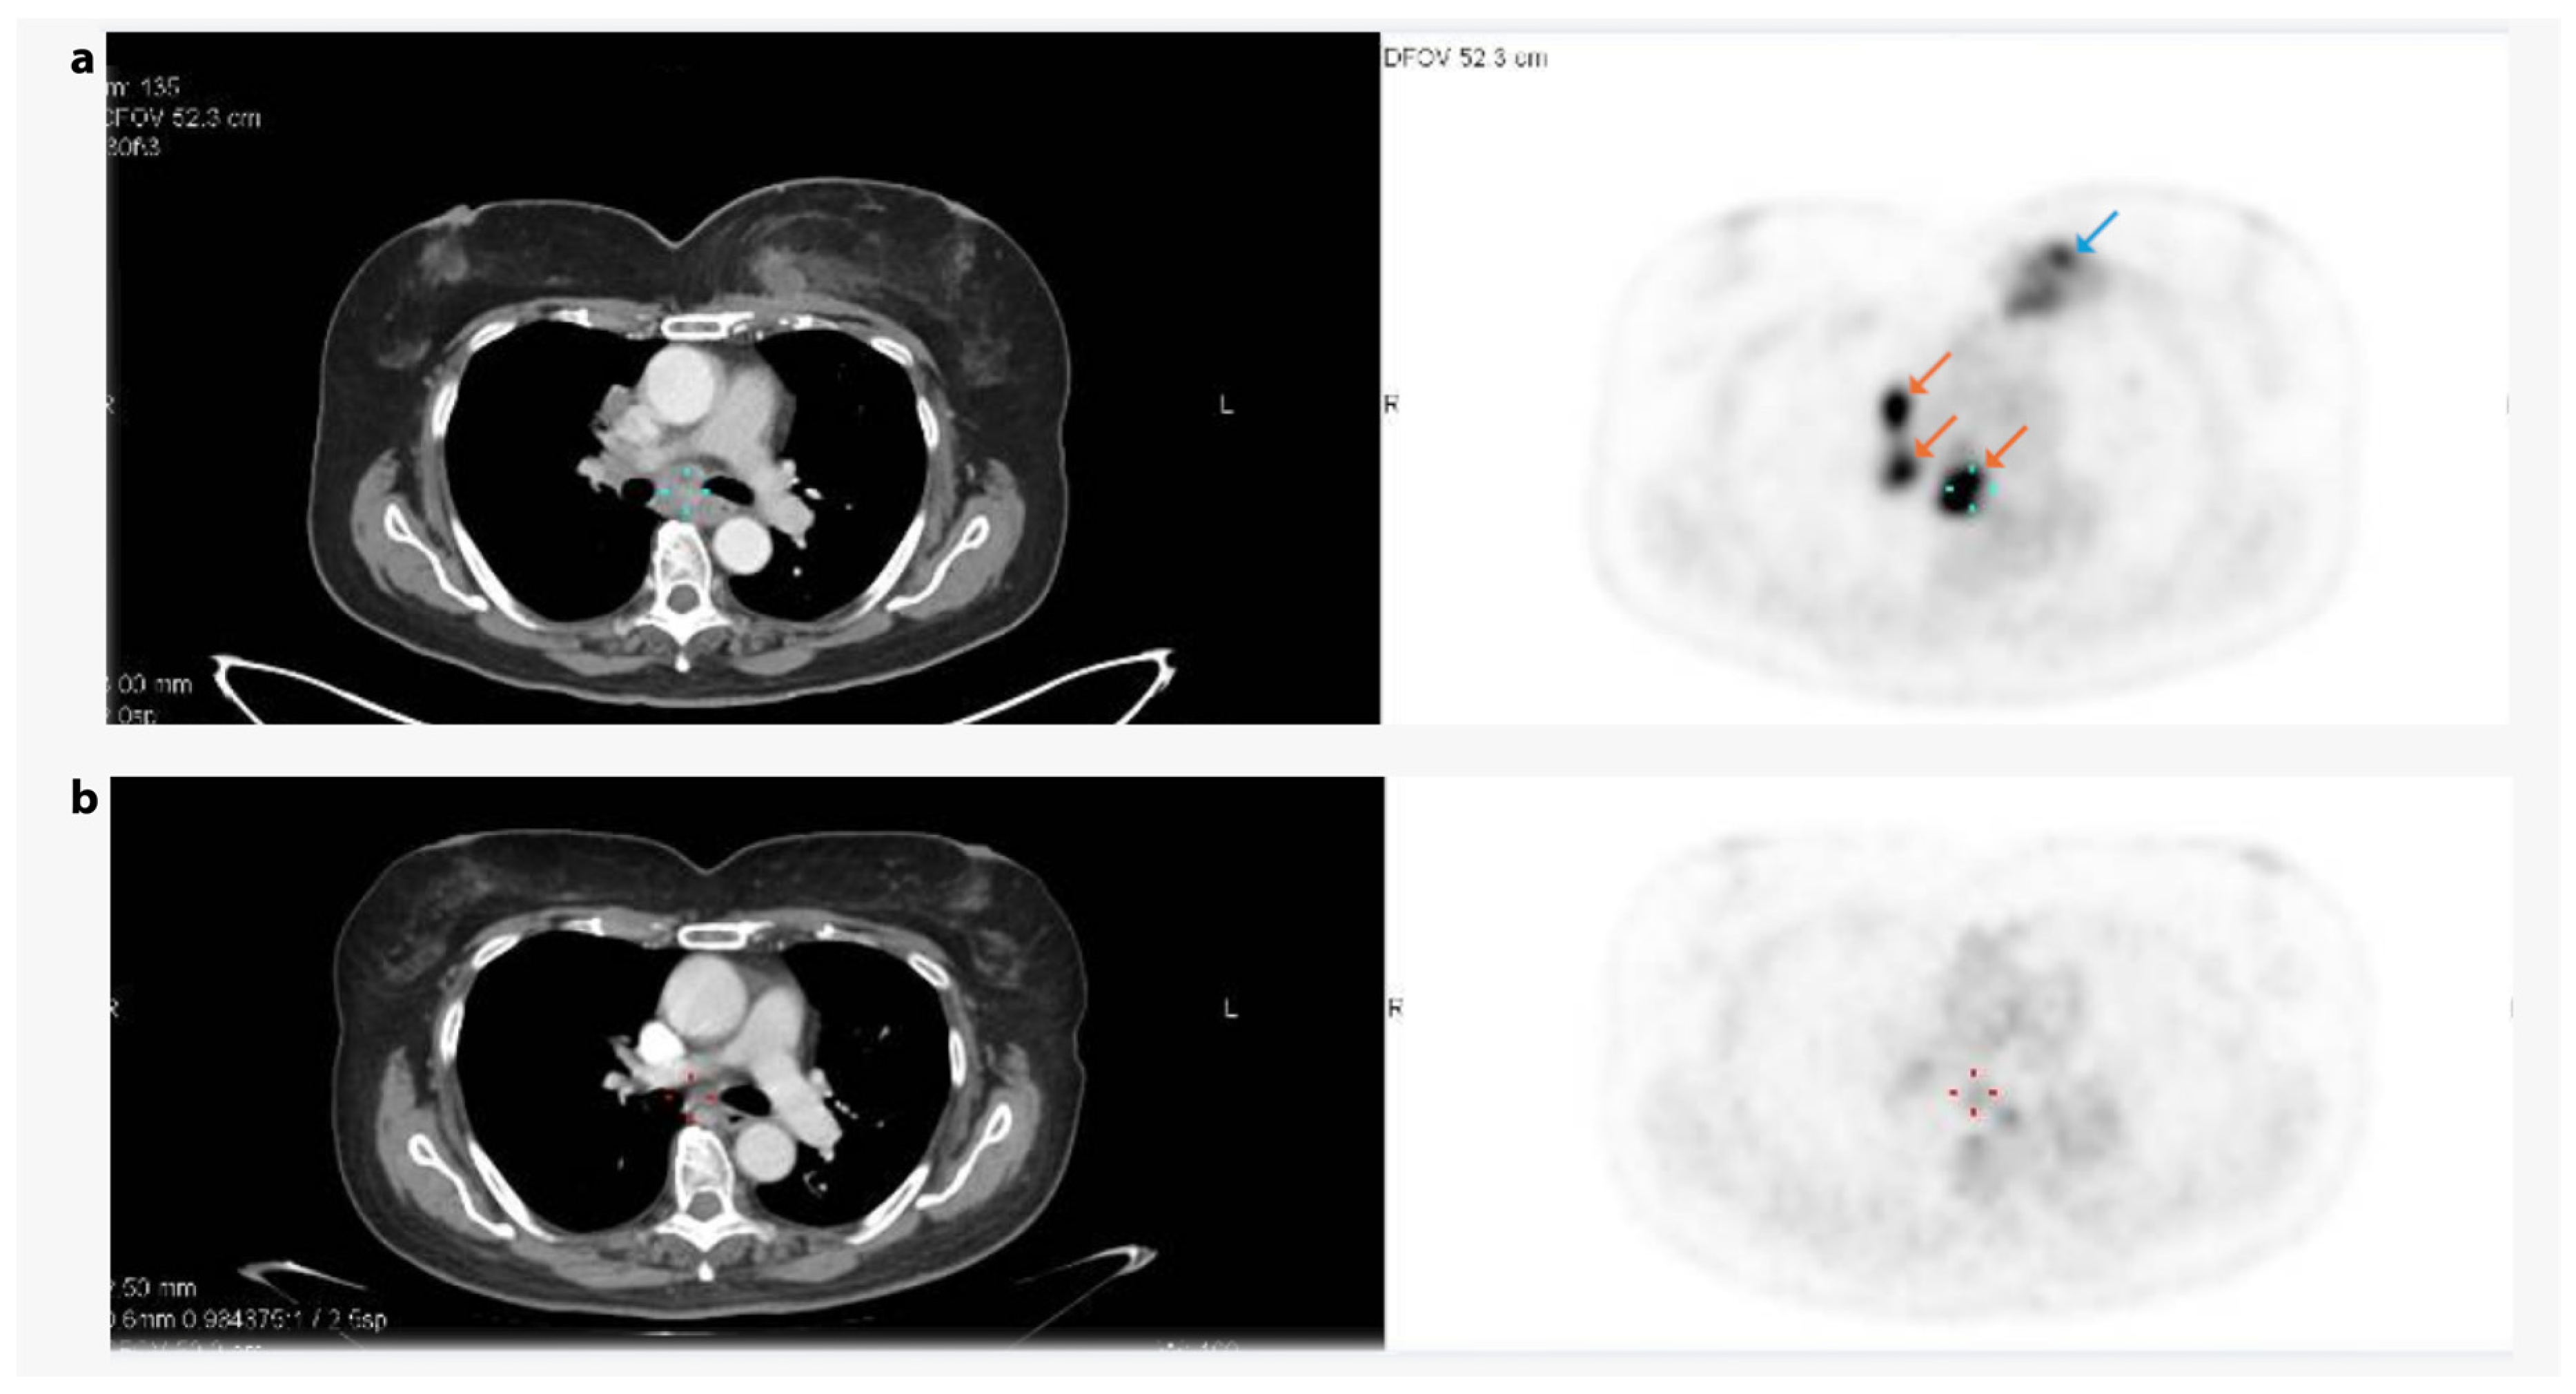

3.6. Case Study